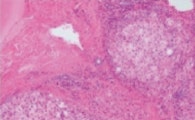

ケーススタディー: 色比較

True Color LEDは実際にどのような標本でその実力を発揮するのでしょうか? True Color LEDの性能を、同一染色の組織標本を使って、一般的な市販の白色LEDとの直接比較によって視覚的に評価しました。(図2: ヘマトキシリン・エオジン(HE)染色及びアザン・トリクローム(Azan Trichrome)染色例。)

図 2: ハロゲンランプと各種LED光源の比較

True Color LED照明は、HE染色標本(a-d)及びアザン染色標本(e-h)のいずれにおいても、ハロゲンランプとほぼ同等の色再現性を有しますが、他の市販の白色LED光源は演色性が悪い為、ハロゲンランプと異なった色再現となります。